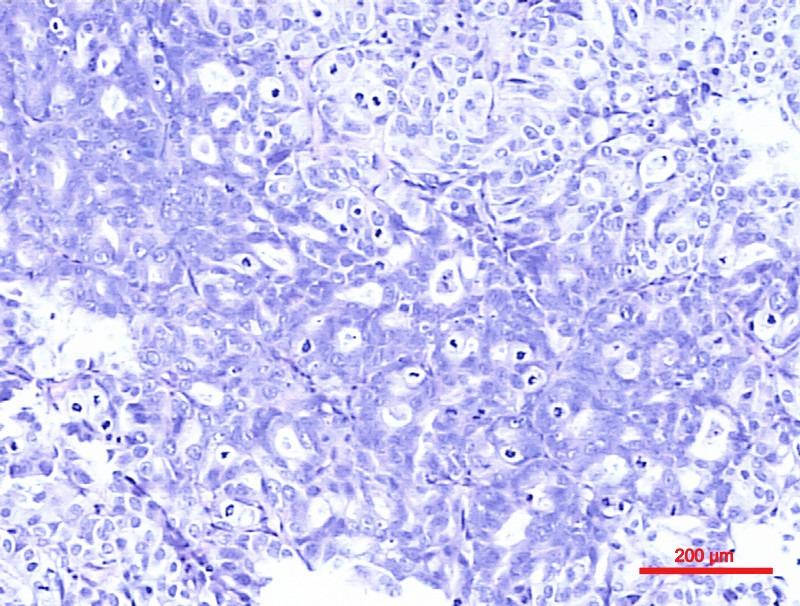

The aim of the present study was to investigate the impact of squamous and/or glandular differentiation on the recurrence and progression in patients with nonmuscle invasive urothelial carcinoma of bladder (NMIUCB) following transurethral resection (TURBT). A total of 869 patients with NMIUCB who had been treated with TURBT at The Second Hospital of Tianjin Medical University (Tianjin, China) between January 2006 and January 2011 were retrospectively selected for the present analysis. Associations among squamous and/or glandular differentiation with other clinical and pathological features were assessed by the χ2 test. Recurrence-free survival (RFS) and progression-free survival (PFS) curves were estimated using the Kaplan-Meier method. Univariate and multivariate analyses were performed through a Cox's proportional hazards regression model. Among the 869 patients, 232 (26.7%) patients had squamous and/or glandular differentiation. High grade tumors were more common in patients with squamous and/or glandular differentiation compared with those with pure urothelial carcinoma of bladder (P<0.001). Associations between age (P=0.115), sex (P=0.184), tumor size (P=0.223), tumor multiplicity (P=0.108), pathological tumor stage (P=0.909) and squamous and/or glandular differentiation were not observed to be statistically significant. There was a significant tendency towards higher recurrence rate and shorter RFS time in patients with squamous and/or glandular differentiation. However, no statistically significant differences were observed in progression rate and PFS between the two groups. The multivariate Cox regression analysis, identified squamous and/or glandular differentiation as an independent prognostic predictor of recurrence (hazard ratio =1.46, 95% confidence interval=1.10-1.92, P=0.008). In the present study, the presence of squamous and/or glandular differentiation was associated with a higher recurrence rate and shorter RFS time in patients with NMIUCB. Squamous and/or glandular differentiation is therefore an independent prognostic predictor of recurrence.

本研究的目的是探讨膀胱非肌层浸润性尿路上皮癌(NMIUCB)患者经尿道膀胱肿瘤电切术(TURBT)后鳞状和/或腺性分化对复发和进展的影响。回顾性选取了2006年1月至2011年1月期间在天津医科大学第二医院(中国天津)接受TURBT治疗的869例NMIUCB患者进行本分析。采用χ2检验评估鳞状和/或腺性分化与其他临床和病理特征之间的关联。使用Kaplan-Meier方法估计无复发生存期(RFS)和无进展生存期(PFS)曲线。通过Cox比例风险回归模型进行单因素和多因素分析。在这869例患者中,232例(26.7%)患者存在鳞状和/或腺性分化。与单纯膀胱尿路上皮癌患者相比,鳞状和/或腺性分化患者的高级别肿瘤更为常见(P<0.001)。未观察到年龄(P=0.115)、性别(P=0.184)、肿瘤大小(P=0.223)、肿瘤多发情况(P=0.108)、病理肿瘤分期(P=0.9零9)与鳞状和/或腺性分化之间的关联具有统计学意义。鳞状和/或腺性分化患者的复发率有显著升高趋势,RFS时间缩短。然而,两组之间的进展率和PFS未观察到统计学显著差异。多因素Cox回归分析确定鳞状和/或腺性分化是复发的独立预后预测因素(风险比=1.46,95%置信区间=1.10-1.92,P=0.008)。在本研究中,鳞状和/或腺性分化的存在与NMIUCB患者较高的复发率和较短的RFS时间相关。因此,鳞状和/或腺性分化是复发的独立预后预测因素。